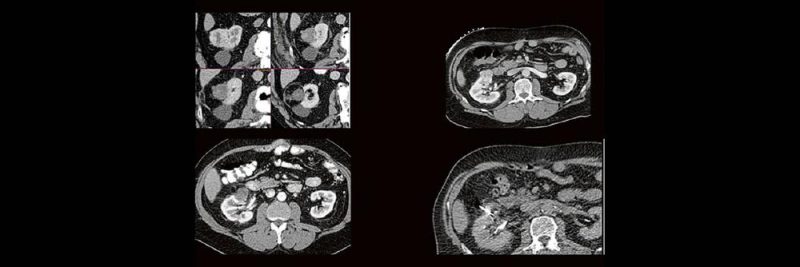

Back to the roots! Gute Kenntnisse der Anatomie sind der Schlüssel zur guten Planung, Durchführung und richtigen Diagnosestellung im CT des Abdomens. Lernen sie unverkrampft

- schnelle Orientierungspunkte für den Alltagsgebrauch

- richtiges Kontrastmittel-Timing im Bild erkennen

- Anatomie in Pathologie übersetzen

Haben Sie es erkannt? Probieren Sie selbst im lockeren Fallquiz zum mitraten.